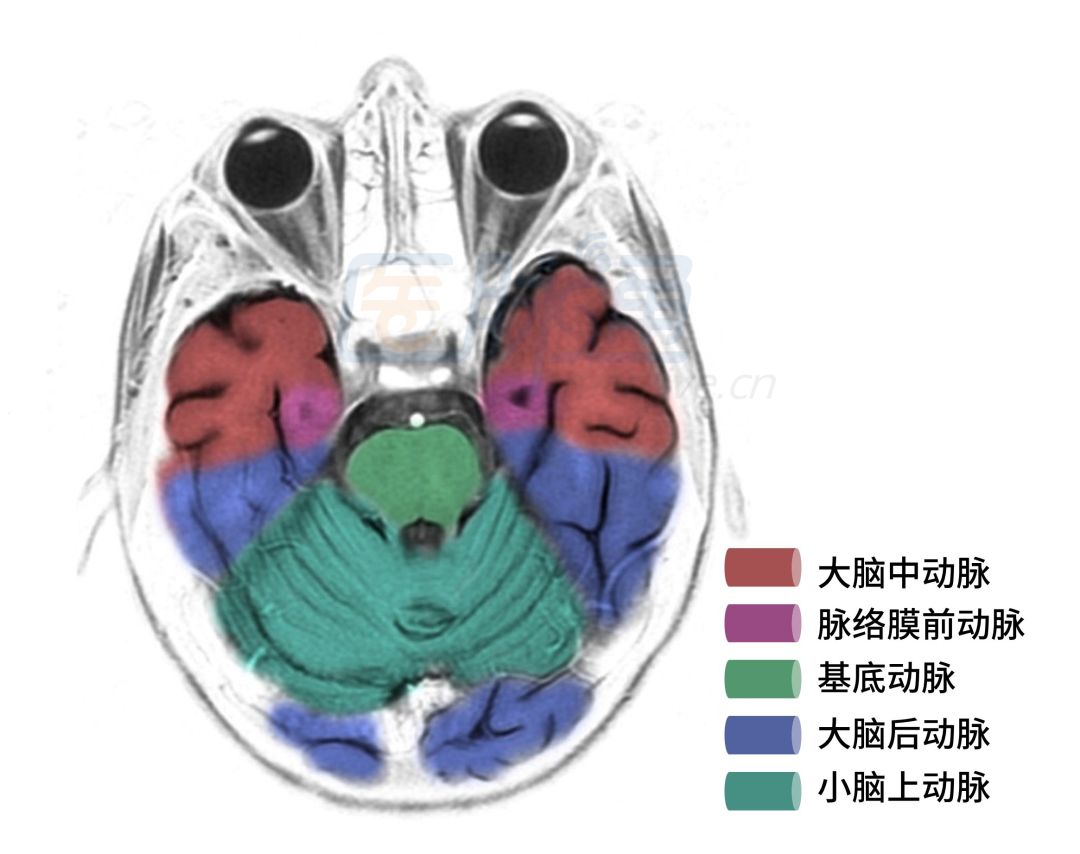

图6 下颞叶层面

图6显示的层面主要是颞叶、脑桥、小脑蚓部、小脑半球等血管供应区域。

❖ 大脑中动脉:其颞下分支供应颞上回,闭塞可引起Wernicke失语;供应颞中回,闭塞可引起命名性失语;供应颞下回,闭塞可引起共济失调和平衡失调。

❖ 脉络膜前动脉:供应内侧颞叶,闭塞可引起神智、情绪、记忆异常,或者癫痫发作、嗅幻觉和味幻觉。

❖ 大脑后动脉:其颞下分支供应颞下回,闭塞可引起共济失调和平衡失调。